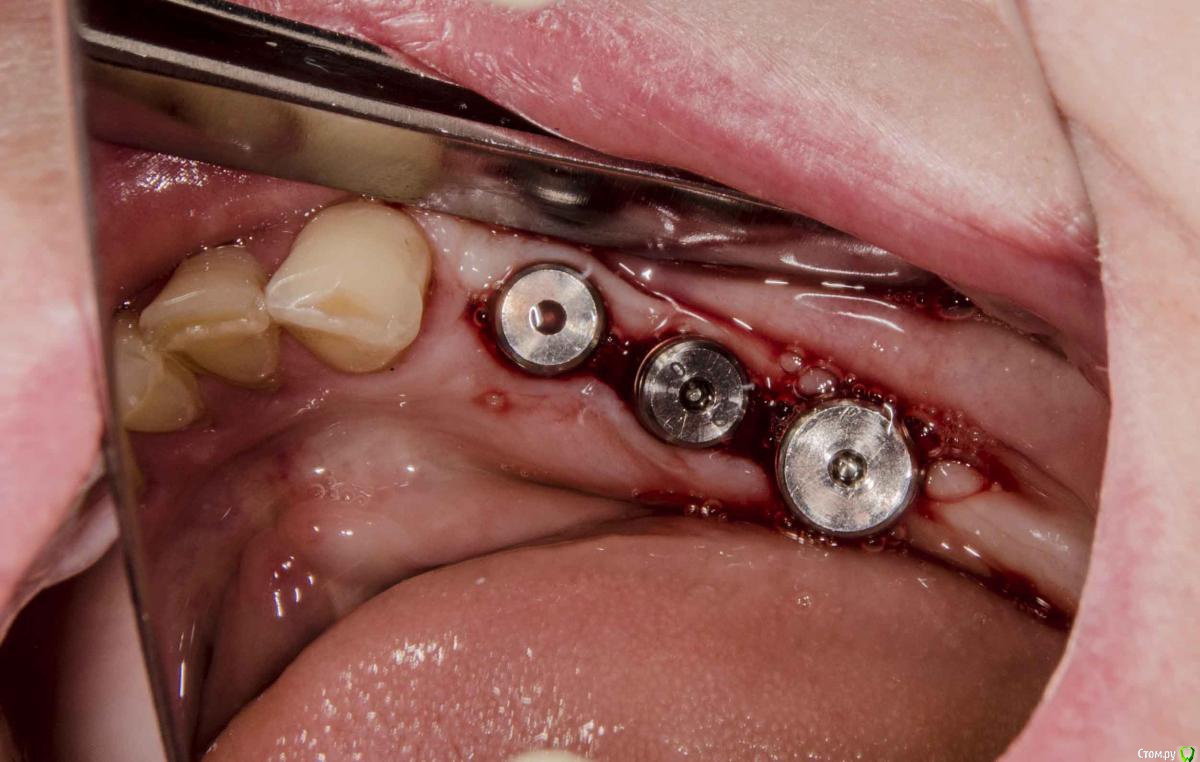

kamranchick Опубликовано 20 декабря, 2015 Поделиться Опубликовано 20 декабря, 2015 (изменено) Добрый день уважаемые форумчане, с наступающим друзья.хотелось бы спросить у Вас, частенько на этапе раскрытия сталкиваюсь с непонятными моментами, а именно, на НЧ иногда когда ушиваю рану получается вот так какая картинатам где не зашивали, картина выглядет более лучше чем там где зашивали)1 этап осмотр через 5 дней. и снятие швов2 этап осмотр через 2 неделиИзвините за качество фото, не умею фотографировать, вскоре этот недуг будет исправлен.Как Вы раскрываете имплантаты если они стоят рядом? точечно или как то по другому?ps работа была произведена давно, теперь там далеко от зубов не отступаю) Изменено 20 декабря, 2015 пользователем kamranchick Ссылка на комментарий

faity Опубликовано 20 декабря, 2015 Поделиться Опубликовано 20 декабря, 2015 вопрос: а зачем вообще были нужны такие большие разрезы? Ссылка на комментарий

kamranchick Опубликовано 20 декабря, 2015 Автор Поделиться Опубликовано 20 декабря, 2015 ну вроде как увеличить КПД, ну и то что рядом стоят они, удобнее... Ссылка на комментарий

Доктор Хаус Опубликовано 20 декабря, 2015 Поделиться Опубликовано 20 декабря, 2015 По фото , где вы зашили лоскут, вы наложили шов так что нарушили питание вестибулярного лоскута . Лоскут ишемизировалься и начал умирать , шов должен только удерживать лоскут так чтобы он не шевелился. И не забывайте о кровяном сгустке . Ссылка на комментарий

andrey_1965 Опубликовано 22 декабря, 2015 Поделиться Опубликовано 22 декабря, 2015 А какими швами рекомендуете фиксировать лоскуты?в Соседней ветке Карэн тоже узловые наложил)) либо дело в толщине.Дело не столько в типе шва,сколько в рефлекторном желании свести " встык",неизбежен "перетяг" при установки ФДМ таких размеров.Если так непреодолимо стремление к абсолюту- то что мешает бережно поискать заглушки трансгивгивально,затем стандартный формирователь-расширяющий формирователь-временная коронка?Сложно,кто б спорил,зато прикрепление цело и шить не надо. Ссылка на комментарий